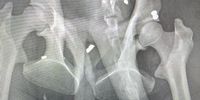

X-rays revealed that besides the injuries from a reported fight with another male, baboon WF8 – better known as Van Damme – had up to 15 penetrating pellet gun wounds. Pellets had lodged in his abdomen, chest, arms and legs, with one large-calibre pellet lodged in his ear canal, according to the Cape of Good Hope SPCA.